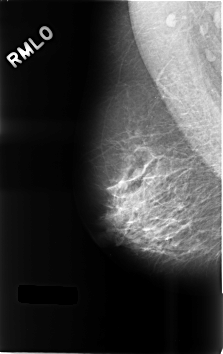

C_0491_1.RIGHT_MLO

RIGHT_CC LINES 4584 PIXELS_PER_LINE 2880 BITS_PER_PIXEL 12 RESOLUTION 50 NON_OVERLAY

RIGHT_MLO LINES 4592 PIXELS_PER_LINE 2888 BITS_PER_PIXEL 12 RESOLUTION 50 NON_OVERLAY